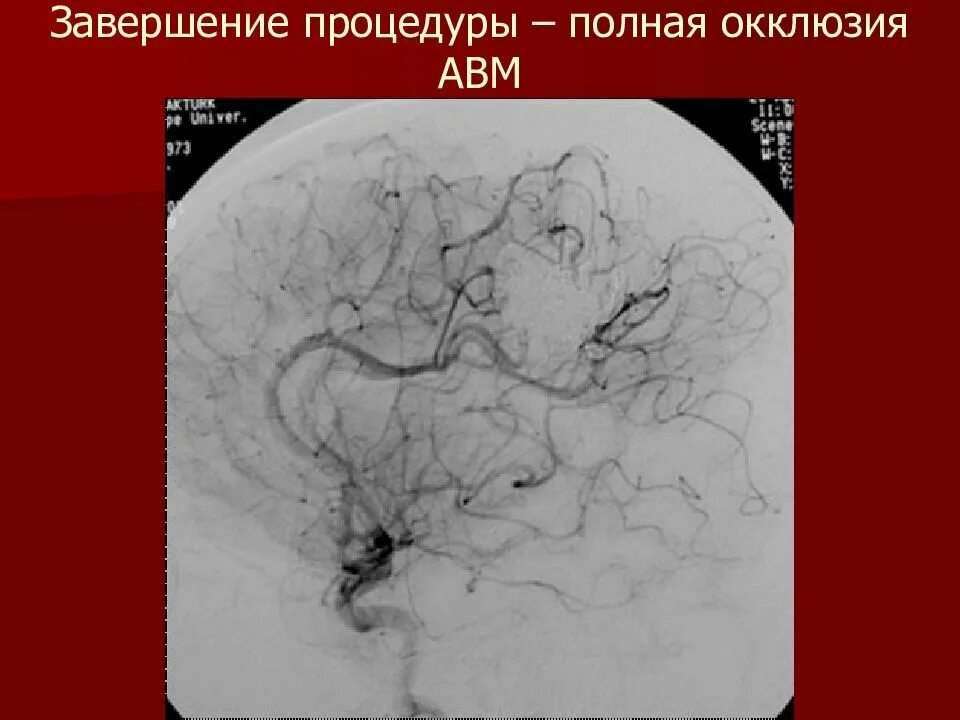

Мальформация сосудов